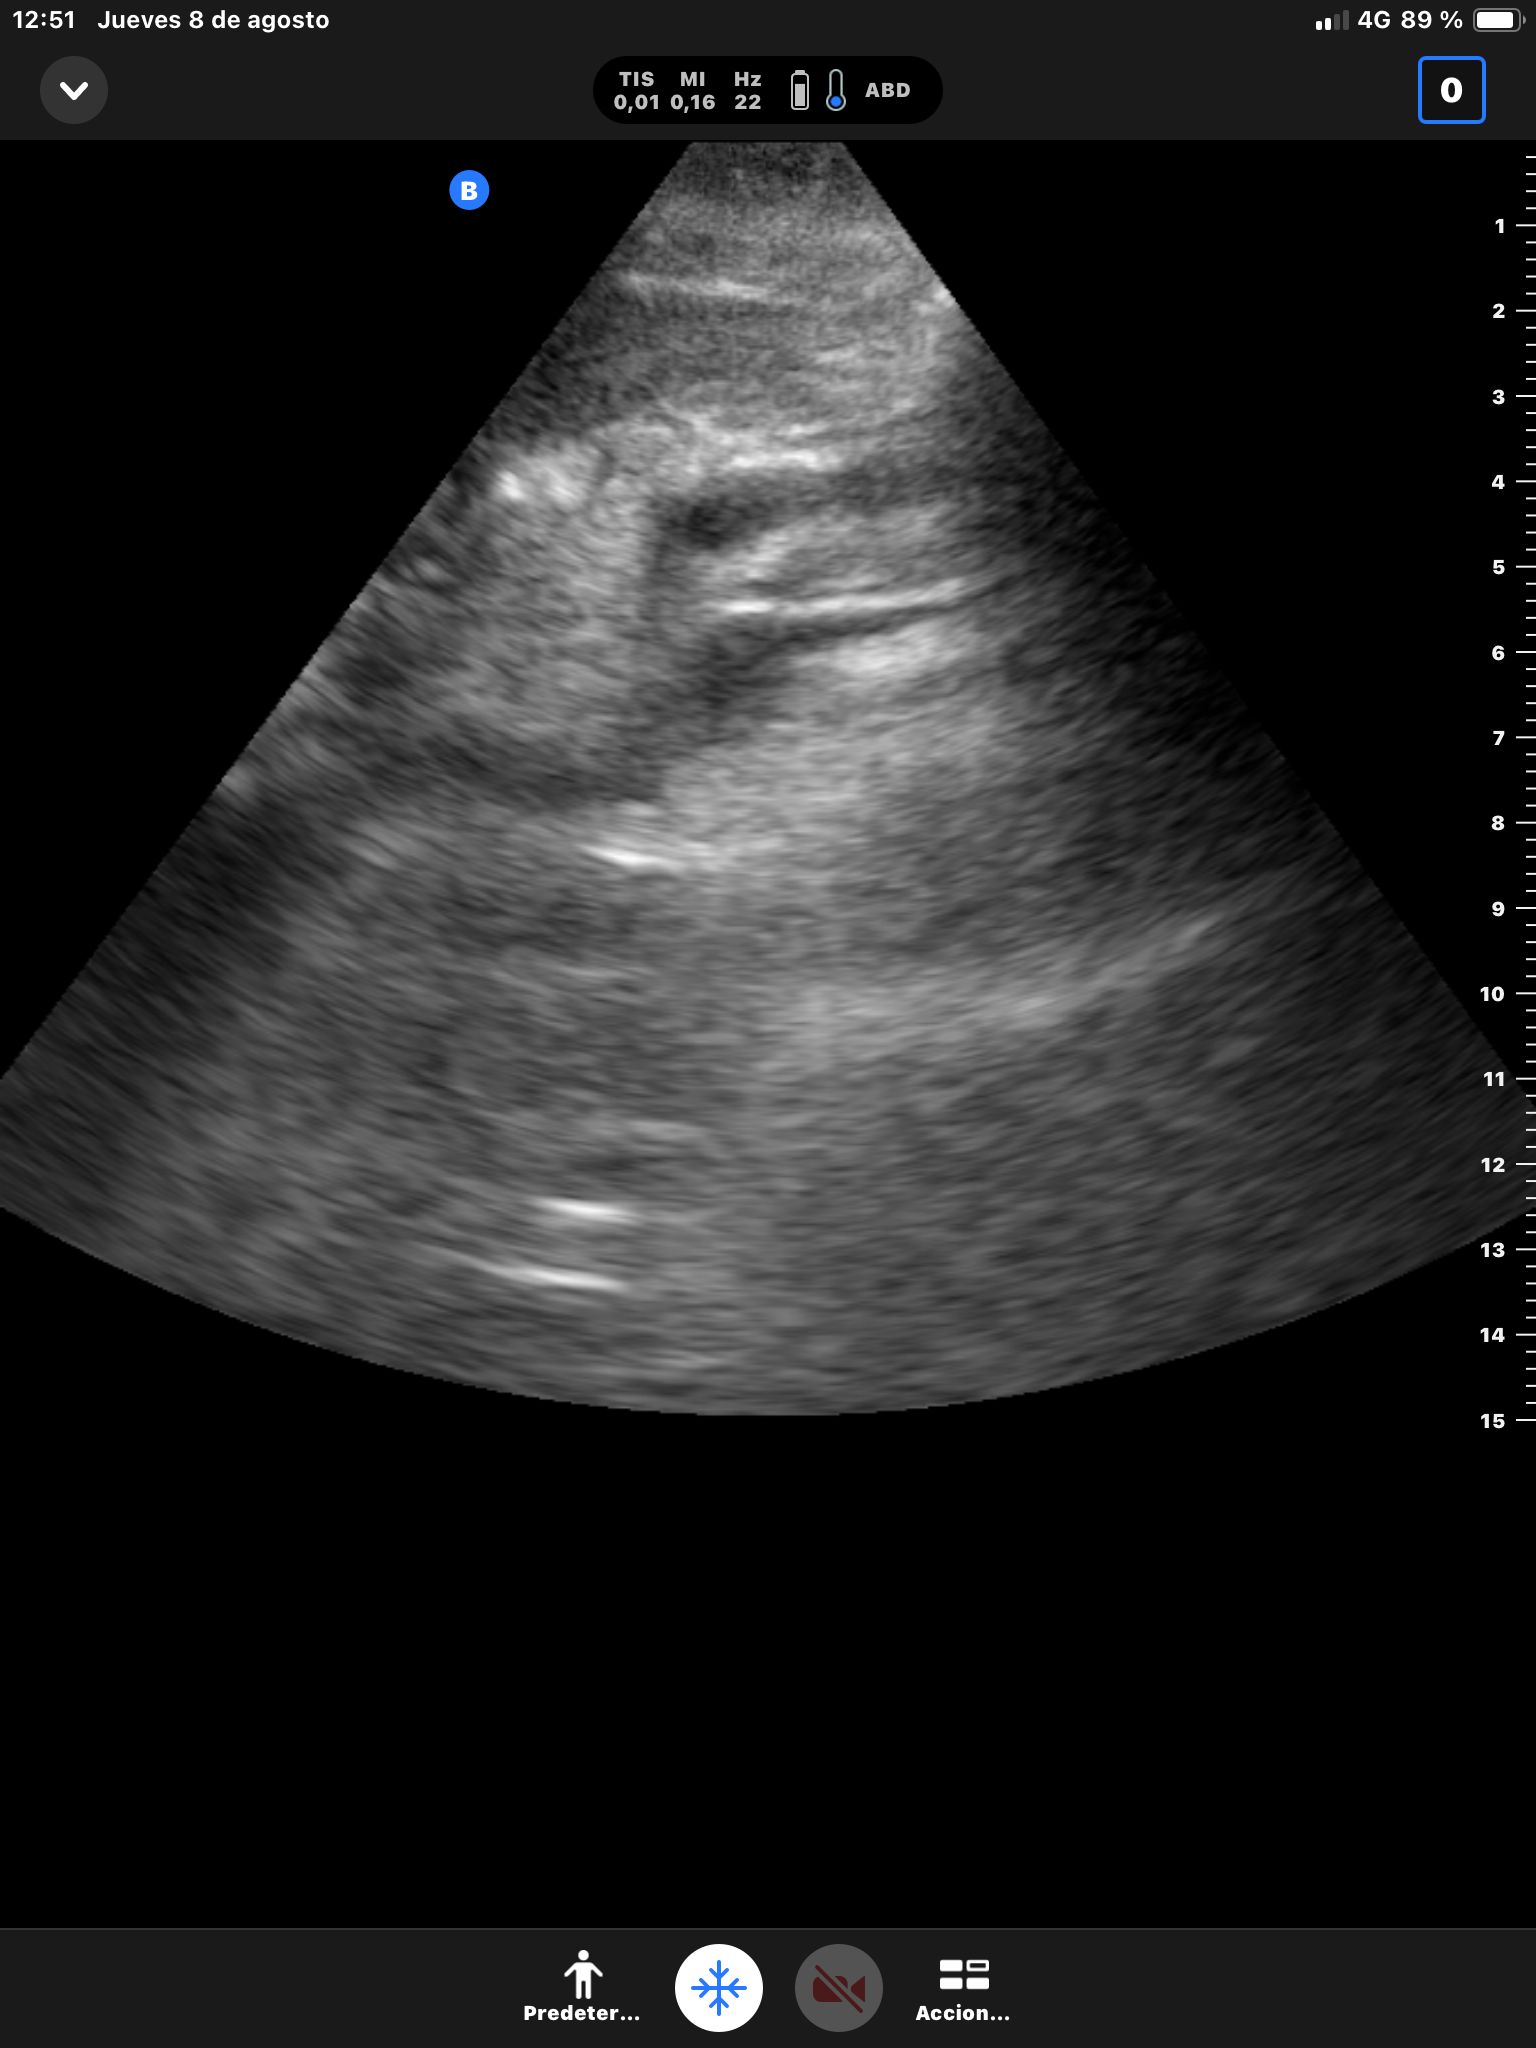

Hígado sin LOEs. Vesícula biliar con hidrops (58 mm), dilatación del colédoco (10 mm). Páncreas hiperecogénico, atrófico, Wirsung de 76 mm.

Dilatación de la vía biliar intrahepática con colédoco dilatado y atrapado por un área hipocaptante sobre la cabeza del páncreas. Atrofia del páncreas con dilatación del conducto de Wirsung que presenta calibres de hasta 8 mm con afilamiento o en el área de la cabeza pancreática.